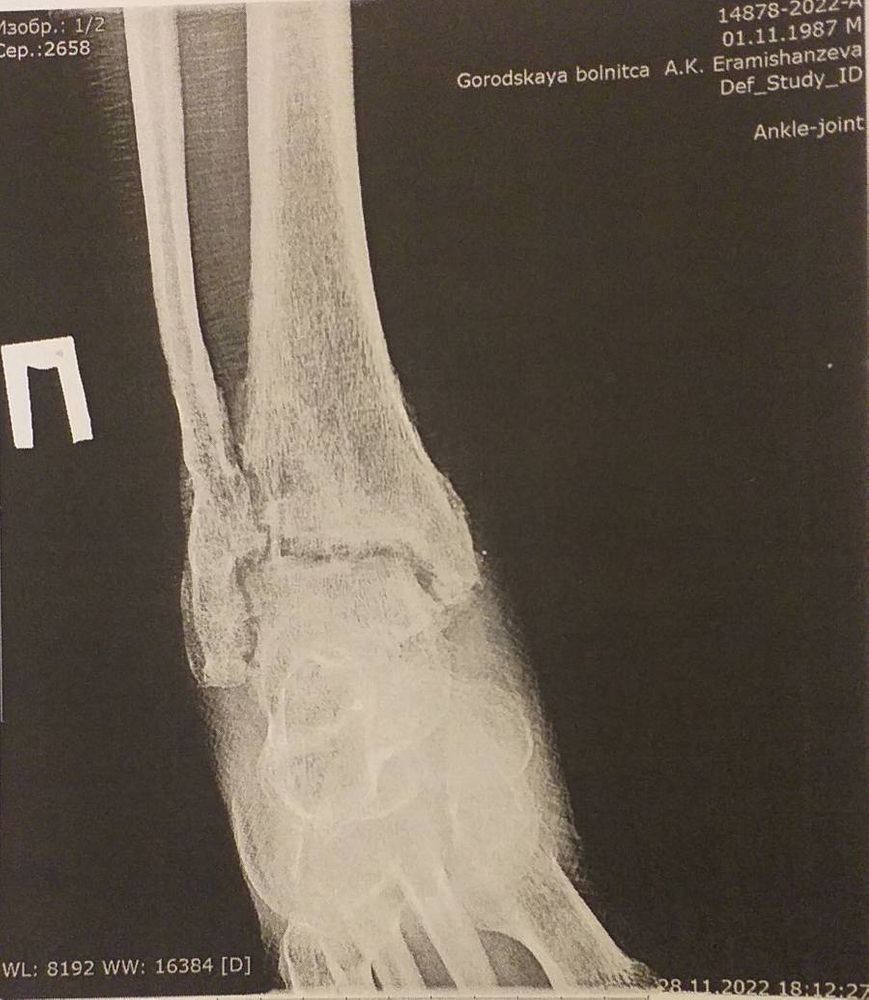

oxana(vogel), потом уже вот так и я в больницу ложусь 19 декабря! Изображение

Марина, кокс не кокс артроз он и в Африке артроз! как ты его не назови остиоартроз или коксартрит или коксартроз это все одно и тоже! вторая стадия артроза, хм... у меня третья стадия, после перелома голеностопа развилась! День ходишь день лежишь! вообще не вариант! Далее гнойный артрит развивается когда, суставная щель исчезнет в суставе и сустав будет воспаляться! Хрящик между суставной исчезает! Вот ложусь на операцию Артродез! Будь что будет! Так жить невозможно с болями! Гори оно все огнем!